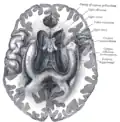

![]() Base of brain (Tuber cinereum visible at center). | |

The tuber cinereum is the portion of hypothalamus forming the floor of the third ventricle situated between the optic chiasm, and the mammillary bodies.[1][2] The tuberal region is one of the three regions of the hypothalamus, the other two being the chiasmatic region and the mamillary region.[1]

Structure

The arcuate nucleus is a part of the tuber cinereum.[3]: 497.e1 The lateral portions of tuber cinereum lodge the lateral tuberal nucleus, and tuberomammillary nucleus. The basolateral aspect of the tuber cinereum often presents slight elevations produced by the underlying lateral tuberal nucleus - the lateral eminence.[1]

The tuber cinereum is situated caudal to the optic chiasm, medial to the optic tract (which flanks it on either side), and rostral to the two mammillary bodies.[4] is continuous anteriorly with the lamina terminalis, and laterally with the anterior perforated substances.